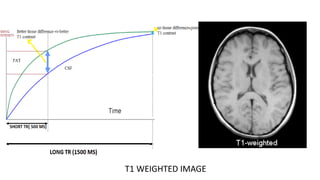

T1 WEIGHTED IMAGE

• Here, the magnitude of the LM indirectly determines the strength of

MR signal.

• Tilting of stronger LM by 90 degree RF pulse greater magnitude

of TM stronger MR signal.

• Tissues with short T1 regain their maximum LM in short time

(after RF pulse is switched off) when next RF pulse is sent

TM will be stronger resultant signal will be stronger.

• Therefore, material with short T1 have BRIGHT signal on T1 weighted

image.

HOW does one make images T1 weighted?

This is done by keeping the TR SHORT.